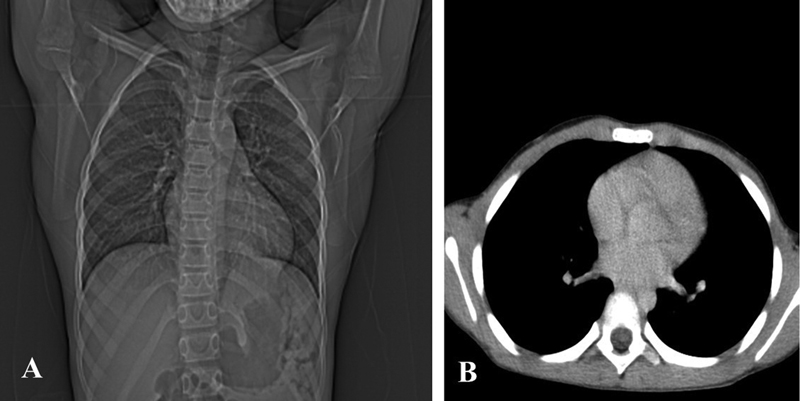

Upon examination, pallor was noted, but there were no signs of icterus, edema, clubbing, cyanosis, or lymphadenopathy. Auscultation revealed decreased breath sounds in the left lower basal area without any other additional sounds, and the rest of the systemic examination was normal. The results of routine hematological and biochemical tests returned to normal. Chest X-ray revealed a mass on the left lower lung. Contrast-enhanced computed tomography (CECT) scan of the chest revealed a large, well-defined, lobulated, heterogeneously enhancing mass in the left lower lobe, adjacent to the descending aorta and the left posterior aspect of the pericardium, measuring 7 × 8.5 × 7.5 cm. There was minimal left pleural effusion ([Fig. 1]). Multiple enlarged, heterogeneously enhancing lymph nodes were observed in the left hilar, subcarinal, left retrocrural, and upper paratracheal regions, with the largest measuring 20 × 20 mm, and a few enlarged lymph nodes in the celiac region.

| Fig 1 : Contrast-enhanced computed tomography of the chest showing an enlarged mass in the lower left lung.